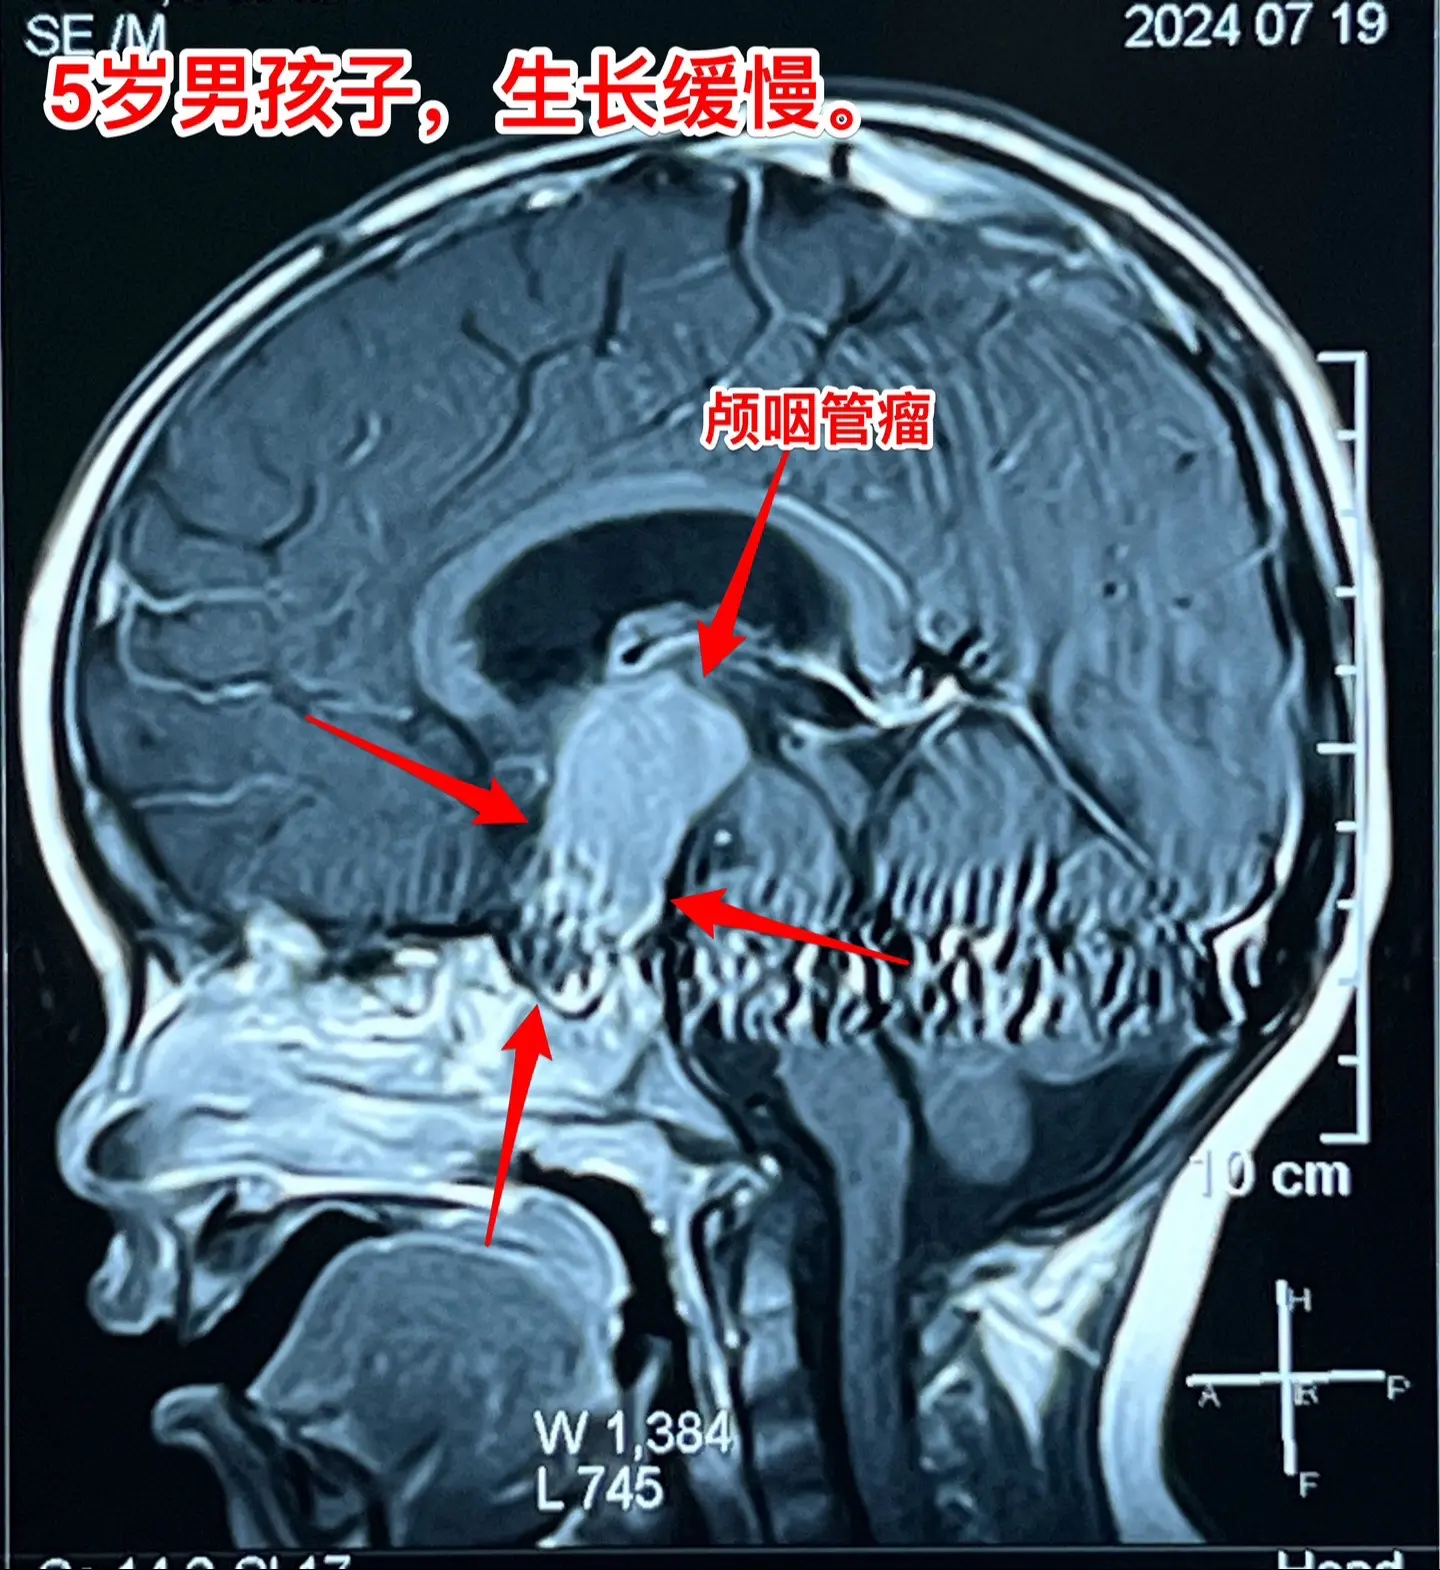

一天两台颅咽管瘤手术对于我们科是常态!7月24日我们科按常规安排了两台颅咽管瘤:第一个5岁男孩子,广东人,因为身高增长缓慢发现了颅咽管瘤。第二个是25岁的三门峡市男性,因为视力下降发现了颅咽管瘤。两个手术都顺利完成。 这样的手术安排对于我们三博脑科医院神经外科八病区来说几乎是常态。有时候一天完成两台复发颅咽管瘤手术,最多的时候一天完成三台颅咽管瘤手术。应该说如果一天只作一个颅咽管瘤手术是比较合理的,一天作两个劳动强度是很高的,不值得提倡。